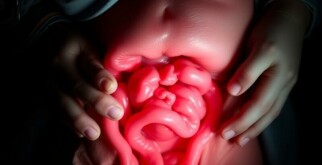

La flora bacteriana implicada en la apendicitis: un mundo microscópico que enciende un órgano olvidado